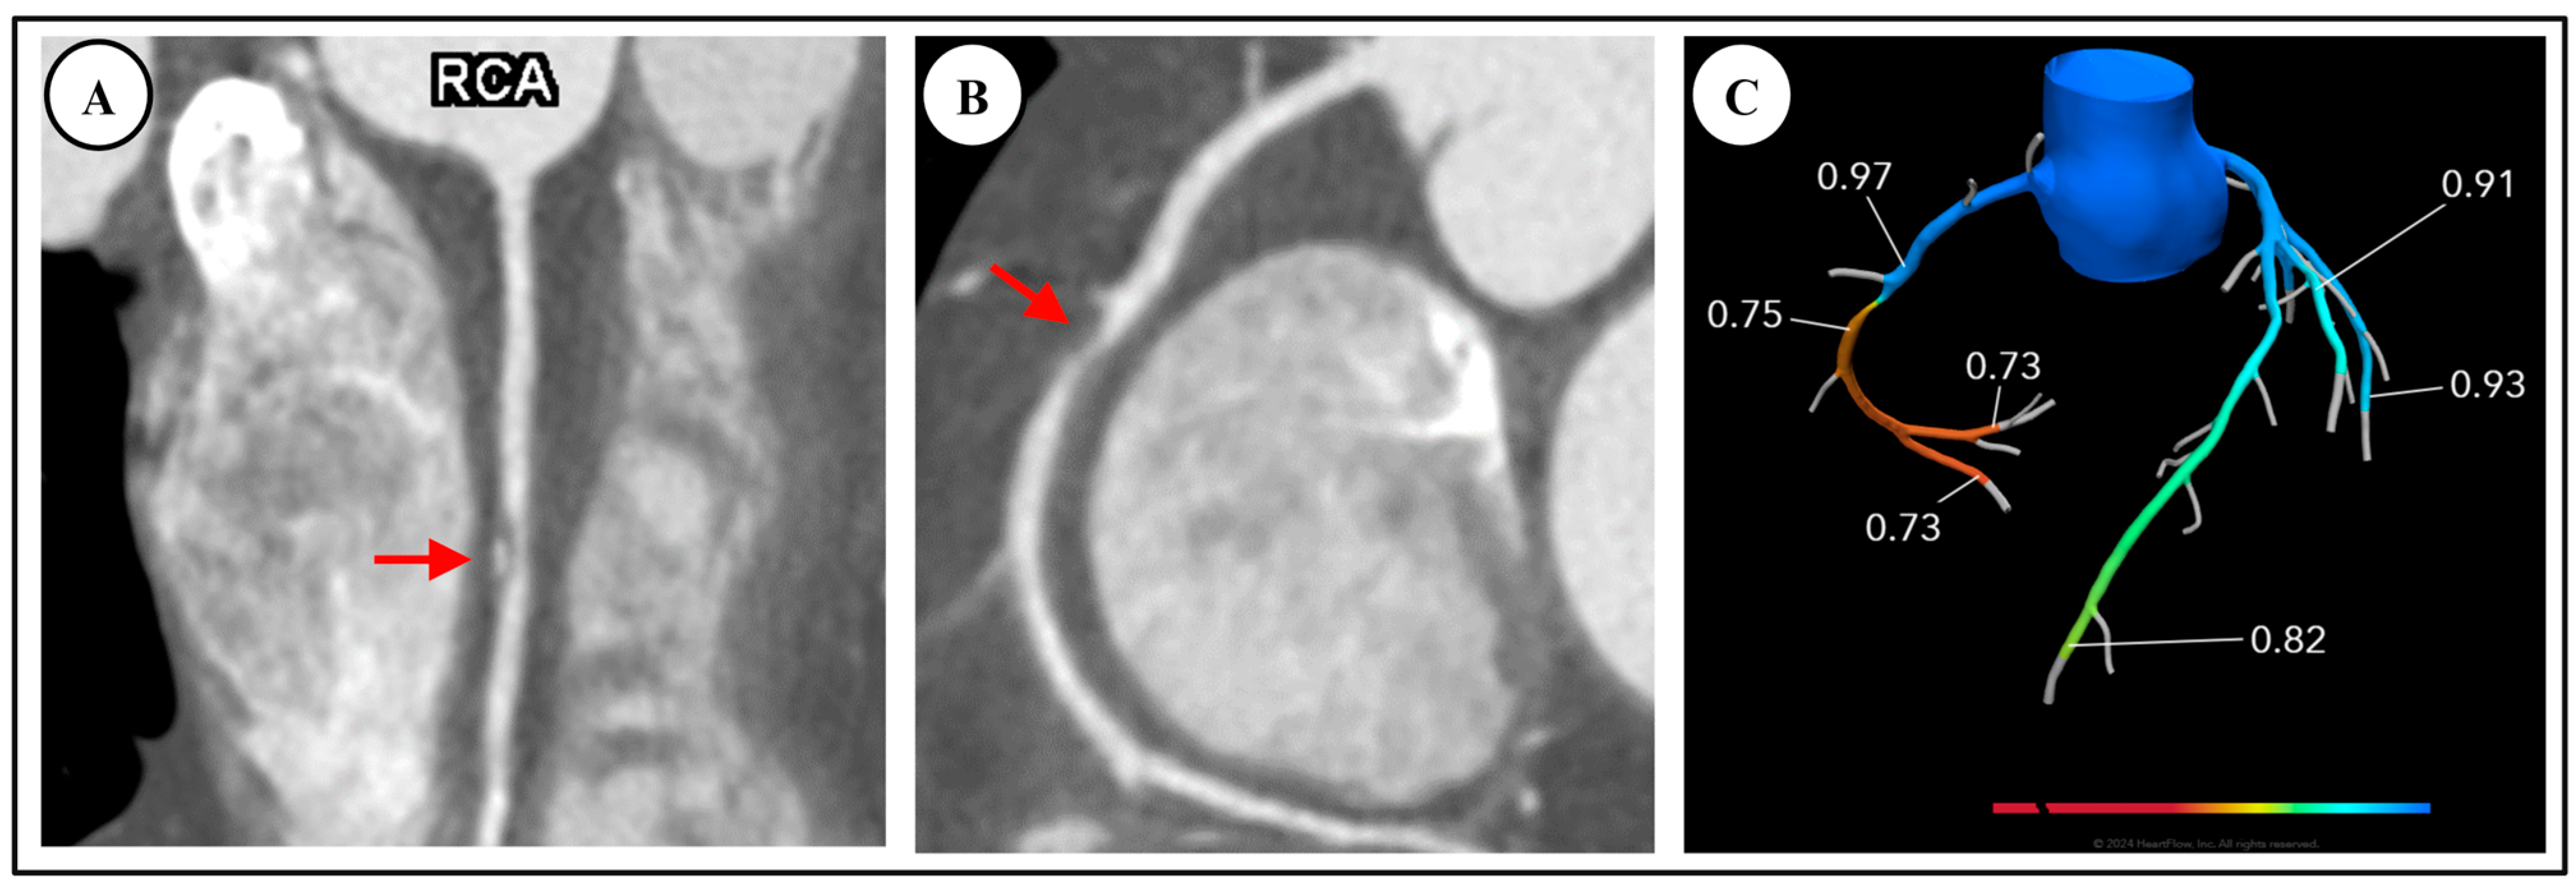

4. Functional Evaluation by CT

4.1. Fractional Flow Reserve—Computed Tomography (FFR-CT)